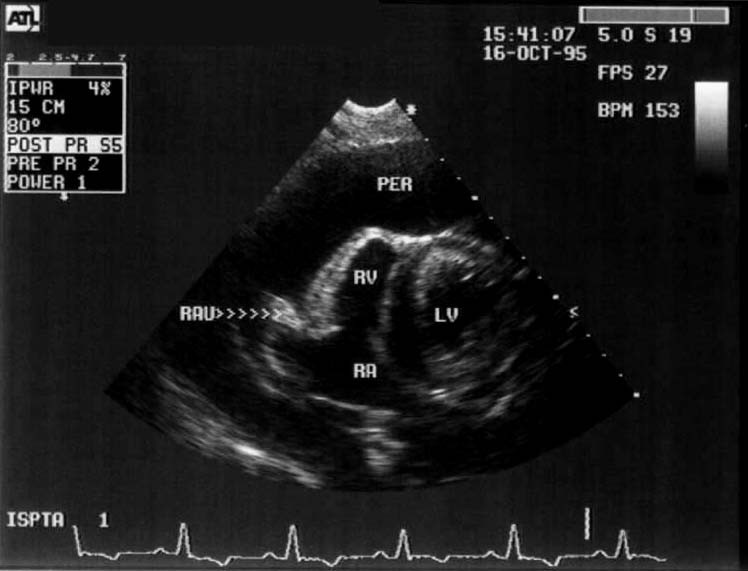

Investigatii clinice si paraclinice : Ecografie abdominala si ecografie toracica, hemoleucograma, biochimie sangvina complete si examen radiologic complet. In urma acestor investigatii s-a descoperit urmatoarele :

• Efuzie pericardica

In urma stabilizarii , Bruno a fost consultat de catre medical cardiolog care a diagnosticat o fisura fina la nivelul peretelui atrial drept ce cauza acumularea de sange in cavitatea pericardica.